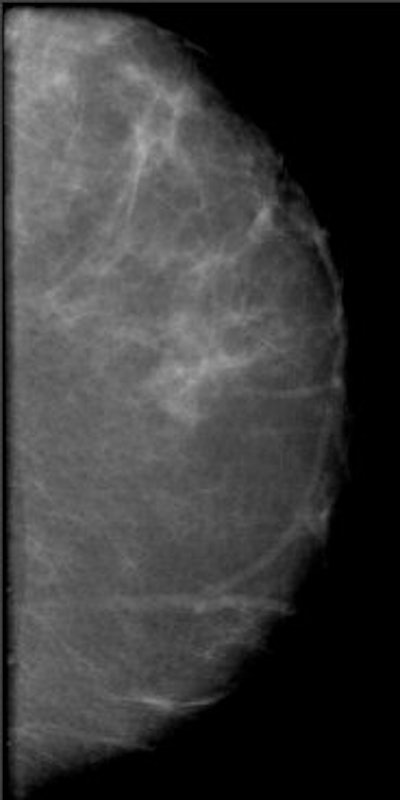

![]() |

| Above, a DBT study in CC and MLO view with a dramatic lesion. Below, DBT study in CC view with two lesions at two different levels. Images courtesy of Dr. Laurie Fajardo, Breast Imaging Research, University of Iowa, Iowa City. |